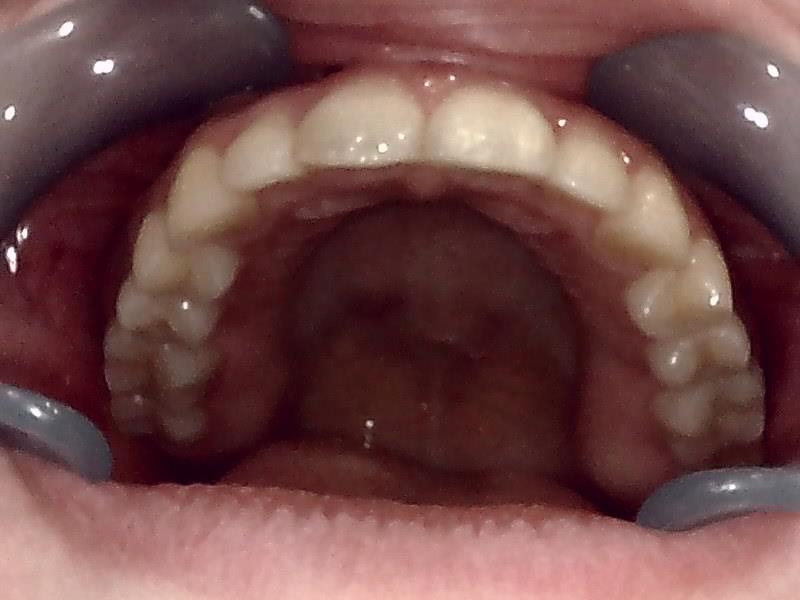

上顎